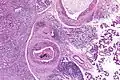

| Low magnification micrograph of a salivary duct carcinoma with characteristic comedonecrosis (left of image) adjacent to normal parotid gland (right of image). H&E stain. | |

Salivary duct carcinoma (SDC) is a rare type of aggressive cancer that arises from the salivary glands.[1] It is predominantly seen in men and, generally, has a poor prognosis.[2] Other high grade carcinomas can mimic SDC. About 40-60% of SDC arise in pleomorphic adenomas.[3] Most, if not all, SDCs express androgen receptor by immunohistochemistry.[4] Therapeutically relevant genetic alterations include ERBB2/Her2 amplification, PIK3CA and/or HRAS mutations.[5][6]

Their histologic appearance is similar to ductal breast carcinoma.